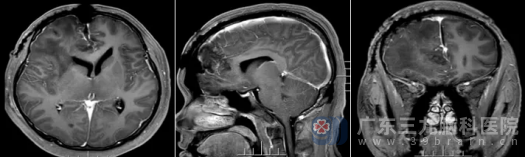

术后复查MR证实:原病变已完全切除。更令人欣慰的是,术后病理诊断为孤立性纤维性肿瘤(CNS WHO 1级)——这是一种预后较好的低级别肿瘤。

术后复查影像